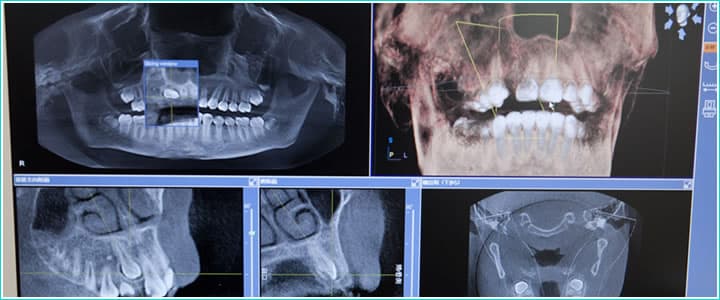

歯科用CTによる精密検査

トラブルなくインプラント手術を実施するためには、事前の検査がとても重要です。当院では歯科用CTによる精密検査を行い、インプラントを埋入する骨や周辺の神経・血管などの状態や位置を事前に把握し、手術に伴うリスクの軽減に努めております。